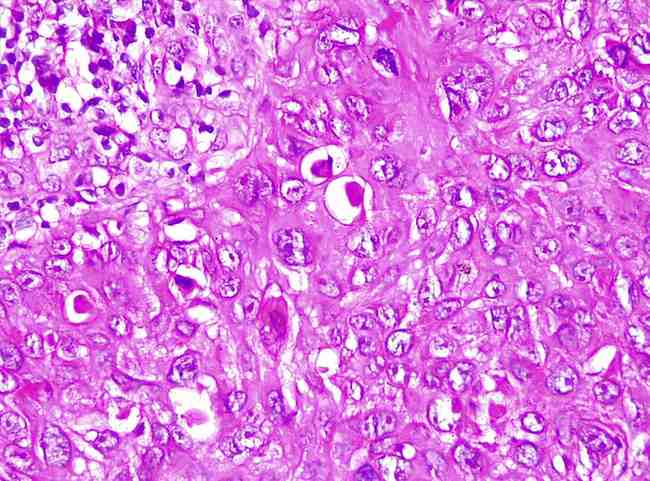

•Melanomas, Primary Tumours & Metastatic Tumours of Skin

•Neoplastic tumours of skin, both primary and metastatic are diagnosed complete with their immunohistochemistry.

⦿ Malignant melanoma diagnosis complete with TNM staging, and IHCs